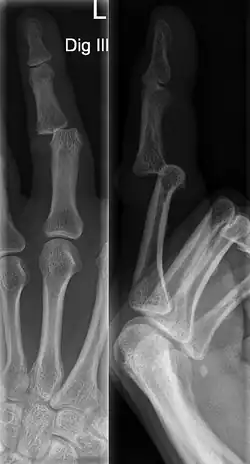

The injured finger may be examined to determine where the pain is worst.[3] If the finger is sprained or dislocated, pain will be worse at the joint rather than the bone.[3] Due to the risk of dislocations or fractures, X-rays should be conducted prior to testing joint stability. This allows for prior detection of a dislocation or fracture.[3] It is recommended that a variety of views (lateral, oblique, and anteroposterior) are observed.[3] In extremely painful cases, a digital nerve block may be done to better assess the finger. This is where anesthetic is injected to either side of the base of the affected finger to reduce pain.[3]

Injuries that force the finger towards the back of the hand may cause damage to the volar plate.[12] This is a ligament on the palm side of the hand that prevents hyperextension.[13] Volar plate damage may be assessed by pressing the finger bones from the back towards the palm. If either individual bone of the affected joint moves freely towards the palm, it is indicative of a tear.[2] Tears of the volar plate may lead to an avulsion fracture – when a piece of bone is pulled off with the ligament.[13] This is due to the thickness and strength of the ligament.[14] To rule out an avulsion fracture, x-rays are frequently utilized in evaluation of suspected volar plate tears.[12] Volar plate avulsions are most evident on lateral views.[2]

Dislocations are often visually obvious due to joint deformity.[2] Therefore, x-rays may or may not be utilized in the diagnosis of a suspected dislocation. Though, they can provide feedback on post-reduction status if attempted prior to formal medical evaluation.[2] Dislocations may also be complicated by a tandem fracture.[5] These cases may necessitate a visit to a hand surgeon for surgery.[2]

Fractures

Fractures are instances where the bone's structural integrity has been compromised.[20] If a jammed finger produces a fracture, pain will be greatest at the bone as opposed to the joint.[2] There may also be visual deformation of the bone itself.[6] As with any skeletal injury, an x-ray can be conducted to verify the presence of a fracture.[1] The distal phalanx is especially vulnerable to avulsion fractures.[1] These avulsion fractures are common following a first time dislocation of the DIP.[1]